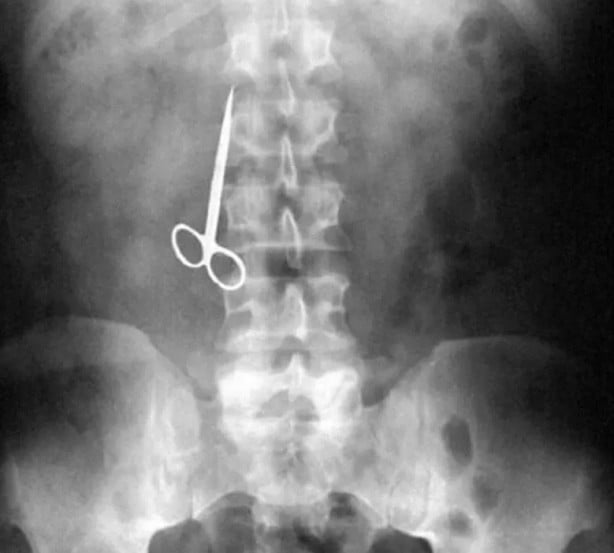

İşte görenleri şaşırtan o röntgen filmleri...